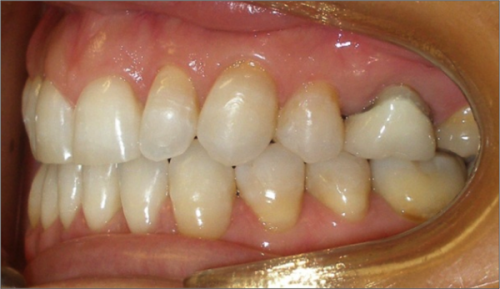

45 year old female:

Diagnosis:

- Missing upper left second bicuspid

- Lower arch crowding

- Edge to edge bite

Treatment:

- Extraction of upper & lower right second bicuspids

- Full fixed appliances

- 21 months